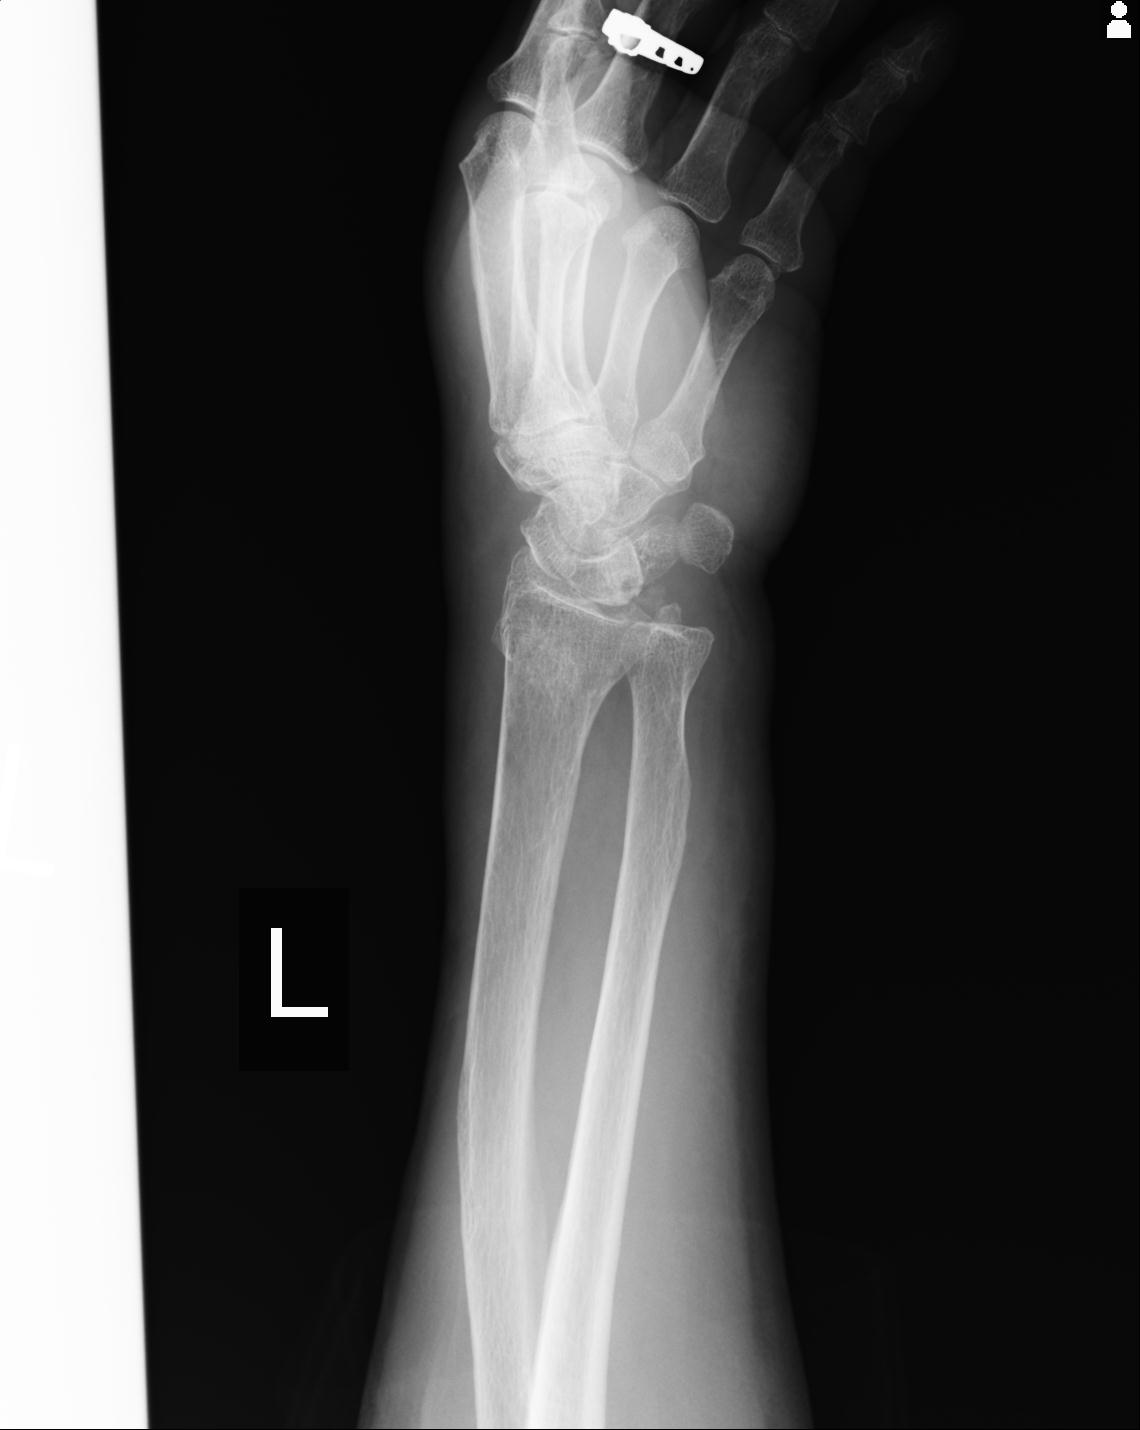

102766 1/5 1/12 左手関節 4R 28歳男性 左橈骨遠位端